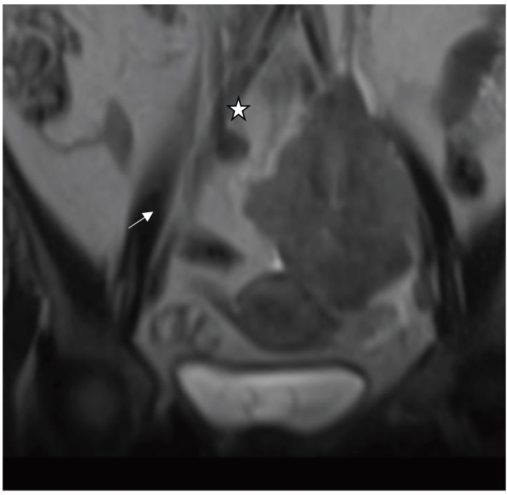

影像学检查提示双侧肾积水。CT 示输尿管周围见大小约9.2×7.8×7.8 cm不均质软组织肿块,包绕输尿管并伴中段输尿管节段性增厚;腹盆腔 MRI 显示左侧盆腔腹膜后见10.8×7.7×5.8 cm梭形分叶状肿块,包绕左侧髂内、外血管,浸润双侧远端输尿管并导致近端输尿管扩张,影像学提示恶性病变,首要鉴别诊断为尿路上皮癌与淋巴瘤。

图1:冠状位T2加权MRI,示盆腔左侧子宫旁一境界清楚、T2中等至高信号肿块(白色星号),邻近子宫(白色箭头)